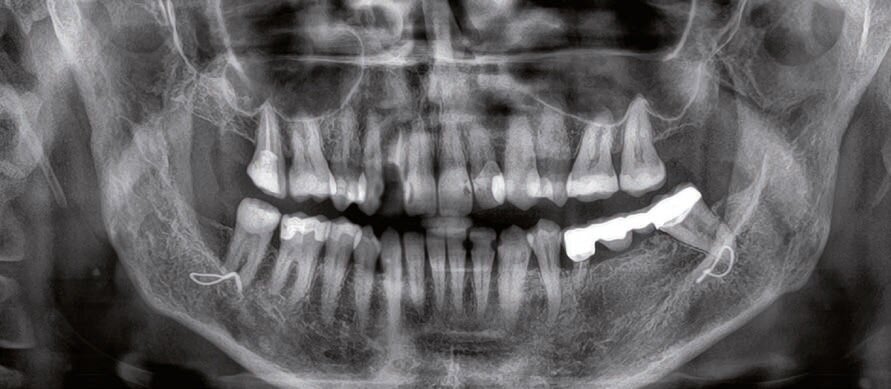

Questo consentirà di sfruttare al meglio la disponibilità ossea in relazione alle necessità protesiche. Per realizzare il sito implantare è stata messa a punto una speciale guida chirurgica, di sezione rettangolare e adeguata alla forma degli specifici inserti piezochirurgici per la preparazione del sito. Si presenta all’osservazione una paziente di 53 anni che presenta mobilità di grado 2 a carico del manufatto protesico 35-x-x-38. Radiograficamente si riscontra un riassorbimento radicolare dell’elemento 35. Si procede ad effettuare una cone beam per l’eventuale sostituzione implanto- protesica degli elementi 35-36-37.

Dalla cbct si evince che la cresta ossea è anatomicamente sfavorevole. Un’ipotesi di piano di trattamento era:

- l’estrazione dell’elemento 35;

- attendere 3 mesi dopo l’estrazione per avere dei tessuti competenti;

- GBR orizzontale;

- attendere 9 mesi rimozione della membrana non riassorbibile e inserimento implantare;

- attendere altri 3 mesi scopertura degli impianti innesto epitelio-connettivale e riposizionamento del fornice;

- attendere 3 mesi e riabilitazione implanto- protesica.

Parallelamente alla proposta di questo piano di trattamento, era stato proposto alla paziente:

- l’estrazione dell’elemento 35 il contestuale inserimento di due impianti REX in 35 e 37 e una GBR vestibolare a scopi puramente estetici in un’unica seduta

- attendere 6 mesi e riabilitazione implantoprotesica.